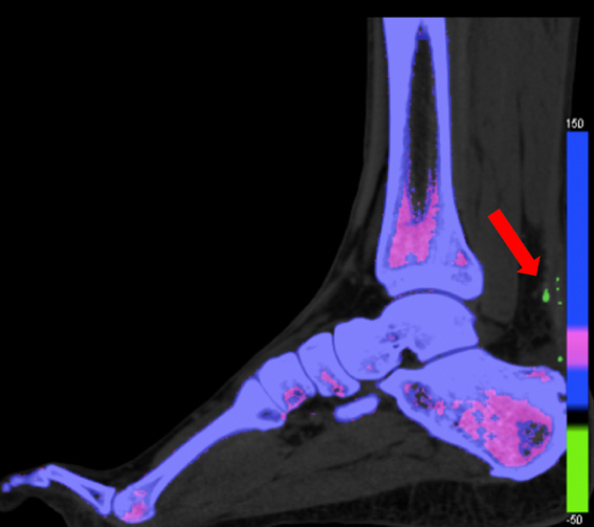

Os principais fatores de risco podem ser divididos em fatores intrínsecos e extrínseco. Os fatores intrínsecos, são aqueles relacionados ao biótipo e anatomia do paciente. e incluem: desvios do eixo do membro inferior, como retropé varo ou valgo em excesso, mobilidade limitada da articulação subtalar e condições sistêmicas, como idade avançada, doenças inflamatórias, diabetes, excesso de peso, doenças metabólicas como a gota (imagem a baixo) por exemplo.

Figura 2: Imagem de TC dupla energia mostrando cristais de gota no tendão de aquiles, em verde, identificado pela seta vermelha.